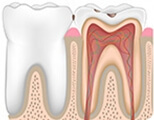

探究牙髓炎、根尖周炎的形成過程

杜牙根是解決牙髓炎、根尖周炎的最佳治療方式

牙神經發炎後感染牙髓組織,從而出現難以名狀的牙疼,影響我們的工作與生活,吃藥僅能短期緩解並不能治癒。所以當您的牙齒出現以下四種不適時,需高度警惕牙體牙髓病變。